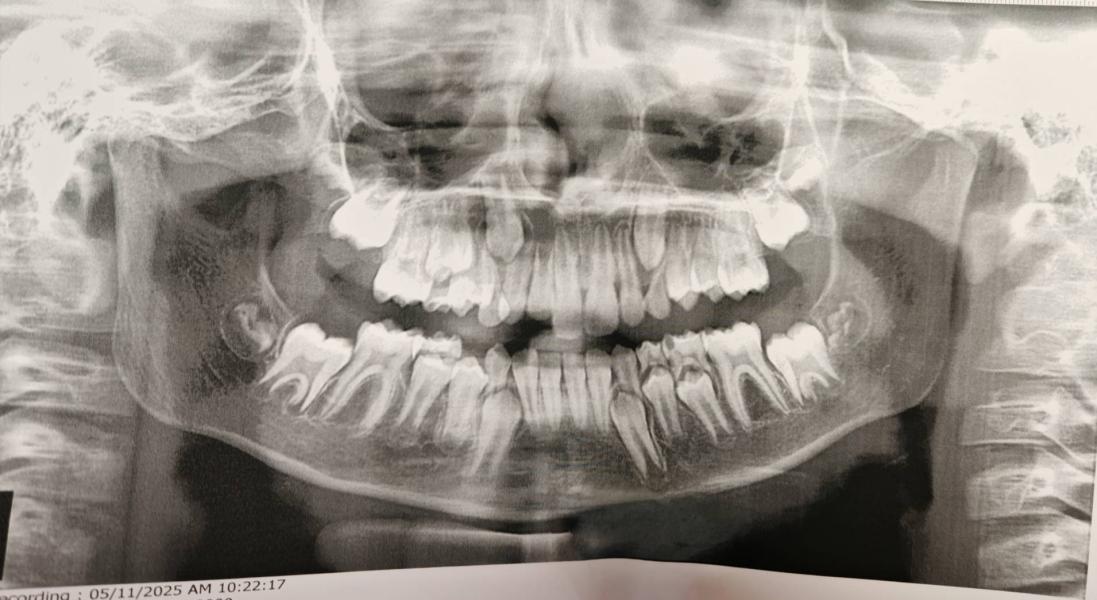

Мой сверхкомплектный многозуб 🫣

Ортодонт вчера выдала направление на КТ на Чайковского, ибо непонятно есть ли корень у зуба, который вроде стоит в дуге, затемнение на снимке - киста это или что вообще... У зуба, который "торчит" сверху есть корень...

Надо дообследовать, чтобы понять, что выдергивать🫣

Картиночка из милого ужастика 😬🦷

Такие снимки у детей прикольные.